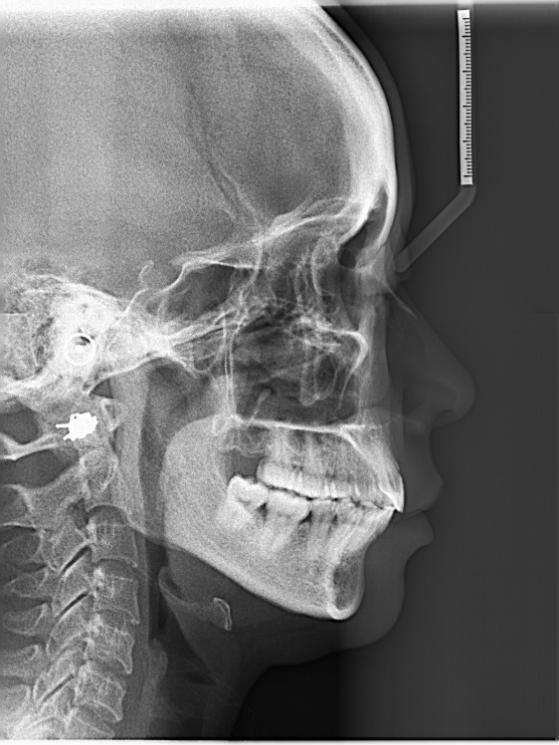

牙齿矫正,其原理就是牙槽骨改建的过程,利用的就是牙齿移动、牙槽骨跟随生长的机制。具体做法就是医生通过矫治器给牙齿施加一个外力,牙齿就会在牙槽骨里缓慢移动,受力侧牙槽骨吸收,受到牵引的一侧牙槽骨增生,以保持牙槽骨正常厚度。此消彼长,所以牙齿是不会松动的。PART 02

首先我们看能不能矫正,不是单纯靠年龄来判断,并不是年龄大的就不能矫正,年龄小的就一定能做。限制牙齿移动的关键不是年龄,而是牙周的健康状况。当然,除了牙周的健康程度外,我们还得考虑牙齿的健康程度、关节的健康程度,以及配合度等问题。在排除以上问题后我们还是建议大家尽早解除自己的牙齿问题的。

年龄虽然不是限制整牙的关键因素,但成人矫正还是有自身限制的。成人毕竟不像小朋友一样,有非常旺盛的生长潜力,那么我们成年人治疗的目标有时相对而言就要放得保守一点,尤其对有骨性问题,牙周不那么健康,关节不那么健康的人而言就不能事事追求完美。

总之,我们的目标就是健康与美,健康永远放在第一位,医生的目标就是寻求两方面的和谐。无论如何,最好的矫治时期就是此时此刻,只要你下定决心,把专业的事交给专业的医生来评估判断,就会收获一个健康美丽的自己。原标题:《“大龄牙套”:成年后正畸靠谱吗? | 贤医健康说》